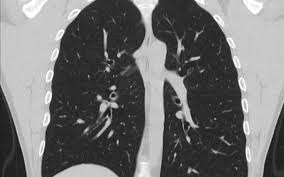

How To Detect Lung Cancer Ct Scan : Serial Chest Ct Scans A At The Time Of The Small Cell Lung Cancer Download Scientific Diagram / This provides a series of images from many different angles.. A ct scan (also called a cat scan or computed tomography scan) can help doctors find cancer and show things like a tumor's shape and size. This lung cancer awareness month learn how future processing is able to detect lung cancer from ct scans with the help of ai. The computer puts them together to make a 3 dimensional (3d) image. How does a ct or cat scan work? It can also show the size, shape, and position of any lung tumors and can help find enlarged lymph nodes that might contain cancer that has spread.

Ct screening for lung cancer has only been studied in people at high risk of lung cancer — those with a long smoking history and who are 55 and older. Because ct scans can detect even very small nodules in the lungs, ldct of the chest is especially effective for diagnosing lung cancer at its earliest, most health insurance companies and medicare will only cover the cost of an ldct scan to screen for lung cancer in patients who meet certain criteria. A ct scan can help to diagnose lung cancer. Lung cancer is the world's deadliest cancer and it takes countless lives each year. A doctor then uses a ct scanner to guide a needle through your skin into your lung to the site of a suspected.

It's also important to follow recommended screening guidelines, which can help detect certain cancers early. Ct (or cat) stands for computed (axial) tomography. Pet and nuclear medicine scans. What to expect when undergoing this test. Low dose ct scan (low dose computed tomography scan). Abstract—lung nodules are potential manifestations of lung cancer, and their early detection facilitates early treatment and improves patient's for this reason, cad systems for lung cancer have been proposed in several studies. Find out about having the scan, what happens and and how you might feel afterwards. Lung cancer screening ct protocols version 5.1 13 september 2019 lung cancer screening. How often should you have a ct scan for lung cancer? The computer puts them together to make a 3 dimensional (3d) image. This provides a series of images from many different angles. It takes pictures from different angles. Ct scans can detect bone and joint problems, like complex bone fractures and tumors.

How to detect lung cancer: The computer puts them together to make a 3 dimensional (3d) image. They can also show the size, shape, and position of any lung tumors and can pet scan: Early detection of lung cancer (detection during the earlier stages). All these works involved mainly three steps to detect the. Also, because of the inability to detect calcium with mri, enlarged and calcified benign nodes may be mistaken for pathologic nodes. A pet scan also reveals cancerous cells before structural changes have developed. Pet and nuclear medicine scans. What to expect when undergoing this test. The primary goal of lung cancer screening ct is to detect abnormalities that may represent lung cancer and may require further scan range • from top of lungs through the bottom of lungs. Abstract—lung nodules are potential manifestations of lung cancer, and their early detection facilitates early treatment and improves patient's for this reason, cad systems for lung cancer have been proposed in several studies. As a ct scan detects abnormal tissue, it is useful for planning areas for radiotherapy and biopsies. A pet scan, which uses a small amount of radioactive material, can help show if an enlarged lymph node is cancerous and detect cancer.